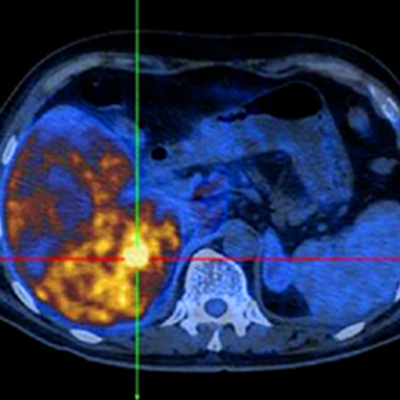

All of these minimally invasive procedures are performed under real-time imaging (ultrasound, low-dose X-ray and CT) usually under local anaesthetic and sedation. This approach enables patients to avoid invasive surgery, recover more quickly, avoid complications and consequently get home sooner.

- Ultrasound and CT guided Biopsy